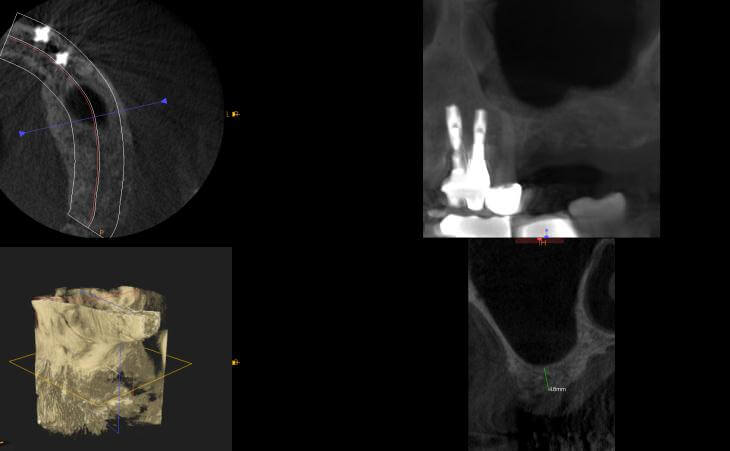

Patient has been missing right and left upper teeth for many years. Bone has deteriorated and a CT scan showed insufficient bone volume for implant placement. The patient underwent Bilateral Sinus Lift surgery and Bone regeneration.

44 year old male missing right and left upper teeth for years decided to have implants placed to replace his upper denture. CT scan determined there was advanced bone loss in the upper jaw under his sinus cavities. Bilateral Sinus Lift Bone Graft was performed for implant placement.

Pt presented with bone loss upper left jaw and wanted to have implants placed. A ct scan determined insufficient bone for implant placement. The patient underwear a Sinus lift procedure to regrown the lost bone.